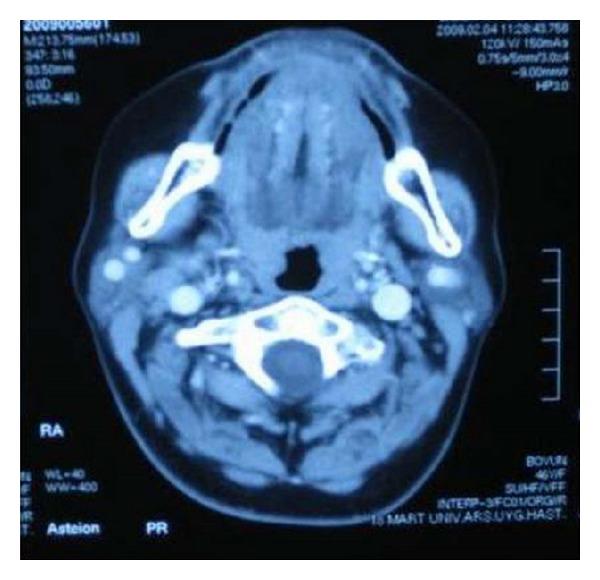

Background. Congenital absence of the submandibular gland (SMG) is a rare condition. Although complaints such as dry mouth, dental problems, or difficulty in swallowing may be seen, the subjects may also be asymptomatic. The absence of the SMG may be associated with hypertrophy of the contralateral SMG. Case Report. We report the case of a 44-year-old woman with incidentally detected left SMG aplasia, with contralateral SMG hypertrophy mimicking a mass, and the case of a 46-year-old woman with incidentally detected bilateral SMG aplasia, demonstrated by computerized tomography (CT) and magnetic resonance imaging (MRI). Conclusion. It is important for the clinician to know that this very rare abnormality may exist. When such a case is encountered, symptoms and findings should be reevaluated and, if necessary, conservative therapy should be initiated. The possibility of observing additional deformities should be kept in mind and an evaluation should be done for other cases in the family.

背景。先天性下颌下腺缺如(SMG)是一种罕见的病症。尽管可能会出现口干、牙齿问题或吞咽困难等症状,但患者也可能没有症状。SMG缺如可能与对侧SMG肥大有关。病例报告。我们报告了一例44岁女性,偶然发现左侧SMG发育不全,对侧SMG肥大类似肿块;以及一例46岁女性,偶然发现双侧SMG发育不全,通过计算机断层扫描(CT)和磁共振成像(MRI)得以证实。结论。临床医生了解这种非常罕见的异常情况可能存在很重要。遇到此类病例时,应重新评估症状和检查结果,必要时应开始保守治疗。应牢记观察到其他畸形的可能性,并对家族中的其他病例进行评估。